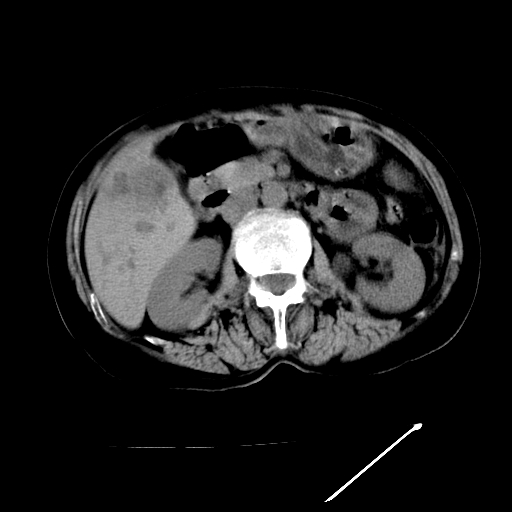

以下是引用随光逐影在2009-4-7 8:21:00的发言:[br]肝内外胆管多发性结石并肝内外胆管扩张;胆系感染。